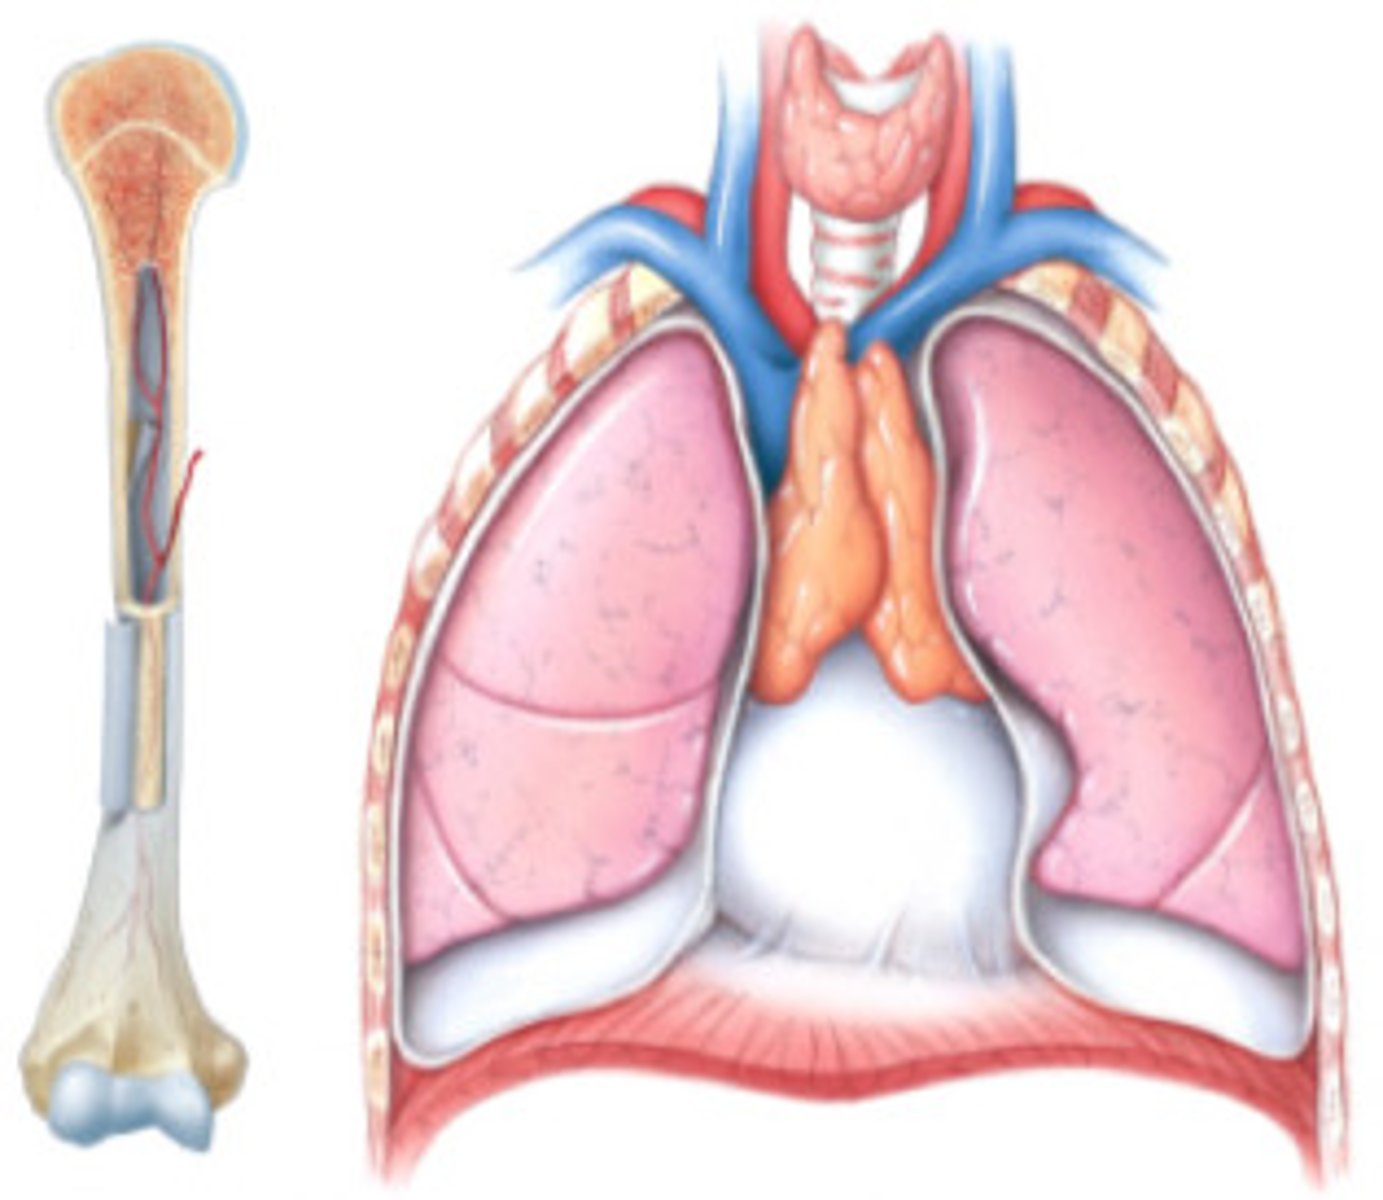

Primary lymphoid tissues

Bone marrow and thymus

What does the bone marrow do?

What does the thymus do?

Site of T cell differentiation and maturation